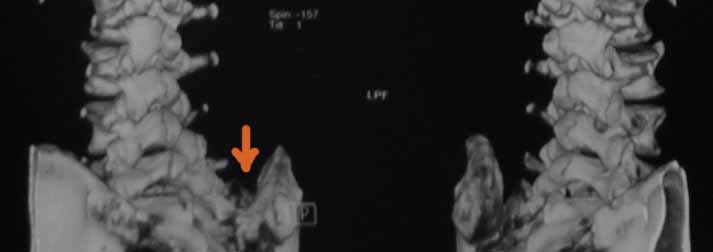

В 2009г установлен диагноз - сакроилеит справа. На представленных КТ имеется гипертрофия заднего отдела правой подвздошной кости с образованием контакта с задней поверхностью крестца. В январе 2011 года выполнена попытка удаления гипертрофированного участка подвздошной кости. удаленные участки кости исследованы гистологически - губчатая кость с элементами гиалинового хряща. После операции положительного эффекта не получено. На контрольной КТ от 04.2011 обнаружено что, желаемого результата операции не получено(интересующий участок удален частично), при этом имеется расслоение заднего отдела правой подвздошной кости.